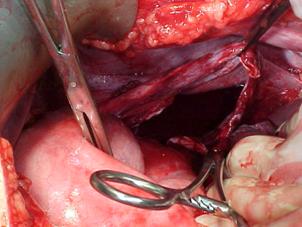

Aspect postsplenectomie Hematom subcapsular

splenic rupt